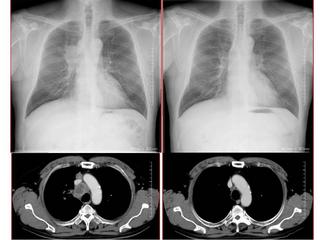

CTで見ると…

3Dだと、こうなります。

気管狭窄ですね。こういう所見もレントゲンで捉えることができるのです。